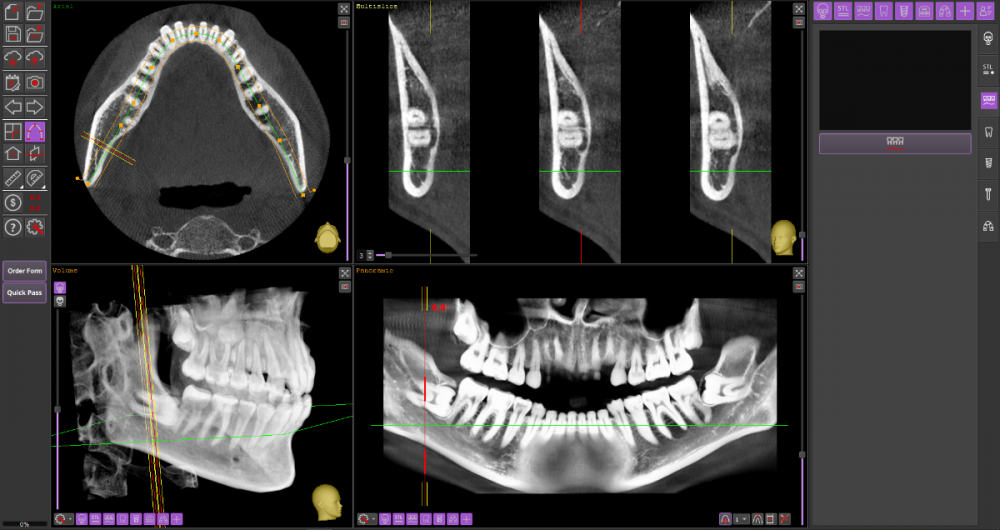

Прошу Вашего совета по поводу удаления восьмых зубов.

Из жалоб есть непродолжительная ноющая боль в правой нижней челюсти, не связанная с внешними раздражителями.

1. Необходимо ли удаление зубов мудрости?

2. Возможно ли удаление амбулаторно, без общего наркоза?

3. Нет ли риска для семёрок при удалении.

DICOM во вложении на Яндекс.Диске https://disk.yandex.ru/d/mBS1B4TYMHIf1A

Виновником боли в н.ч. справа может быть, например зуб 46, не только 48.

1. Удаление 8-х зубов скорее всего необходимо

2. Удаление амбулаторно вполне возможно. Общая анестезия (наркоз) совершенно необязательна, местной анестезии достаточно.

3. Несчастные случаи бывают, но крайне редко.